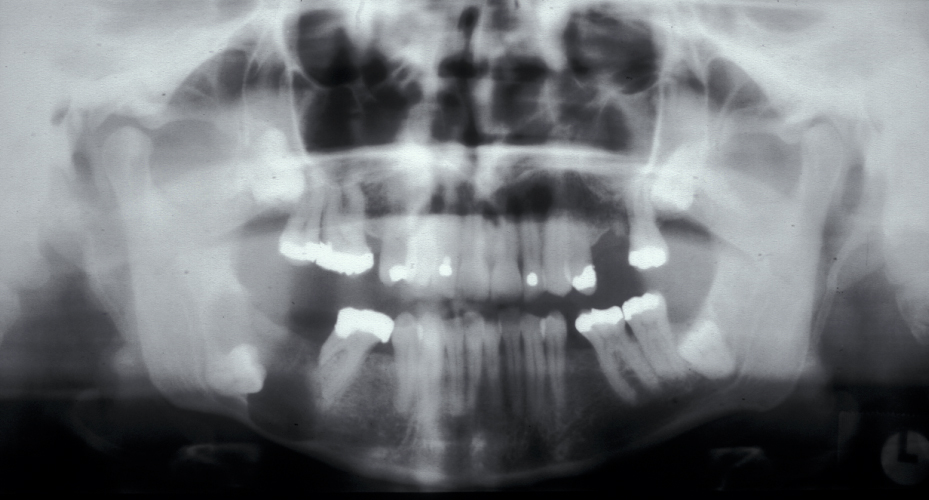

Figure 2 and Figure 3 illustrate examples of indications for removal of a third molar tooth.

Assessment of the tooth is both clinical and radiographic. If somebody presents in pain, it is important to establish that this is coming from the third molar and not elsewhere. Pain is often vague, poorly localised and may be referred from another tooth, or as part of facial arthromyalgia (condition affecting the jaw joint). A dental panoramic radiograph is ideal as it helps to assess all the teeth at once. The health of the adjacent molars may influence the decision whether to remove the third molar or not. Large crowns or old restorations are all at risk of dislodgement during surgery. It is also worth considering whether alternative treatment options are available. For instance, pericoronitis due to an over-erupted upper third molar may be dealt with by extracting that tooth only, with or without operculectomy. In the presence of other teeth of poor prognosis, will it be better in the long term to save the third molar which may be used as a denture or bridge abutment in the future?

These points help to determine whether the tooth can be simply elevated or will need a surgical approach. A series of radiographs depicted in Figure 4 to Figure 8 illustrate these points further.